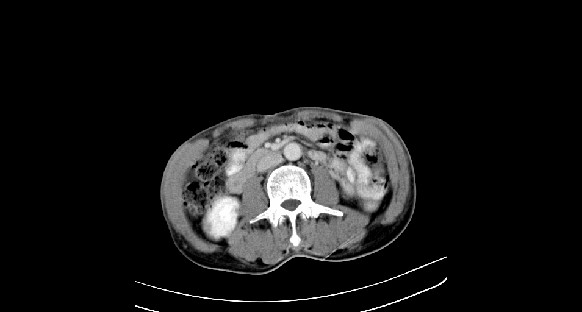

男性,70岁,体检b超发现左肾占位,请各位战友发表一下观点

左肾有两个病灶,且较大的病灶内可见点状钙化灶,增强扫描边缘也是呈渐进性强化,中央部分未见明显强化